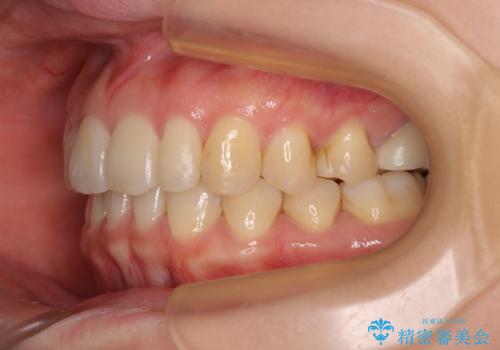

- 上顎前歯の突出感を気にして来院された患者様です。

下顎前歯2本が先天欠損しており、上顎歯列に対して、下顎歯列がアンバランスに小さい状況でした。

左右上顎側切歯2本が矮小歯であるため、上顎の抜歯ではなく、IPR(歯と歯の間を削る)と歯列全体の後方移動によってバランスを整えることとしました。

歯列のバランスが悪く、インビザライン矯正特有の奥歯の噛みにくさがなかなか改善されず、治療期間が長期化してしまいました。